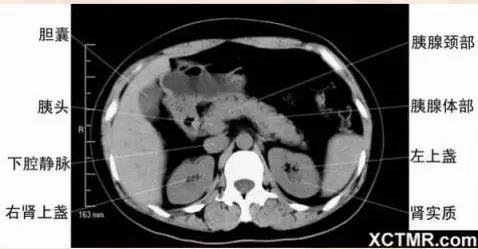

腹部CT